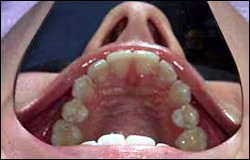

The hard palate and maxillary tuberosity areas are examined using both direct and indirect vision and illumination. Following the visual examination the clinician should digitally palpate the entire area using firm non-sliding pressure against the bone (Figure 27).

Figure 27. Palpating the hard palate.

Use firm pressure and try not to slide the fingers along the tissue.